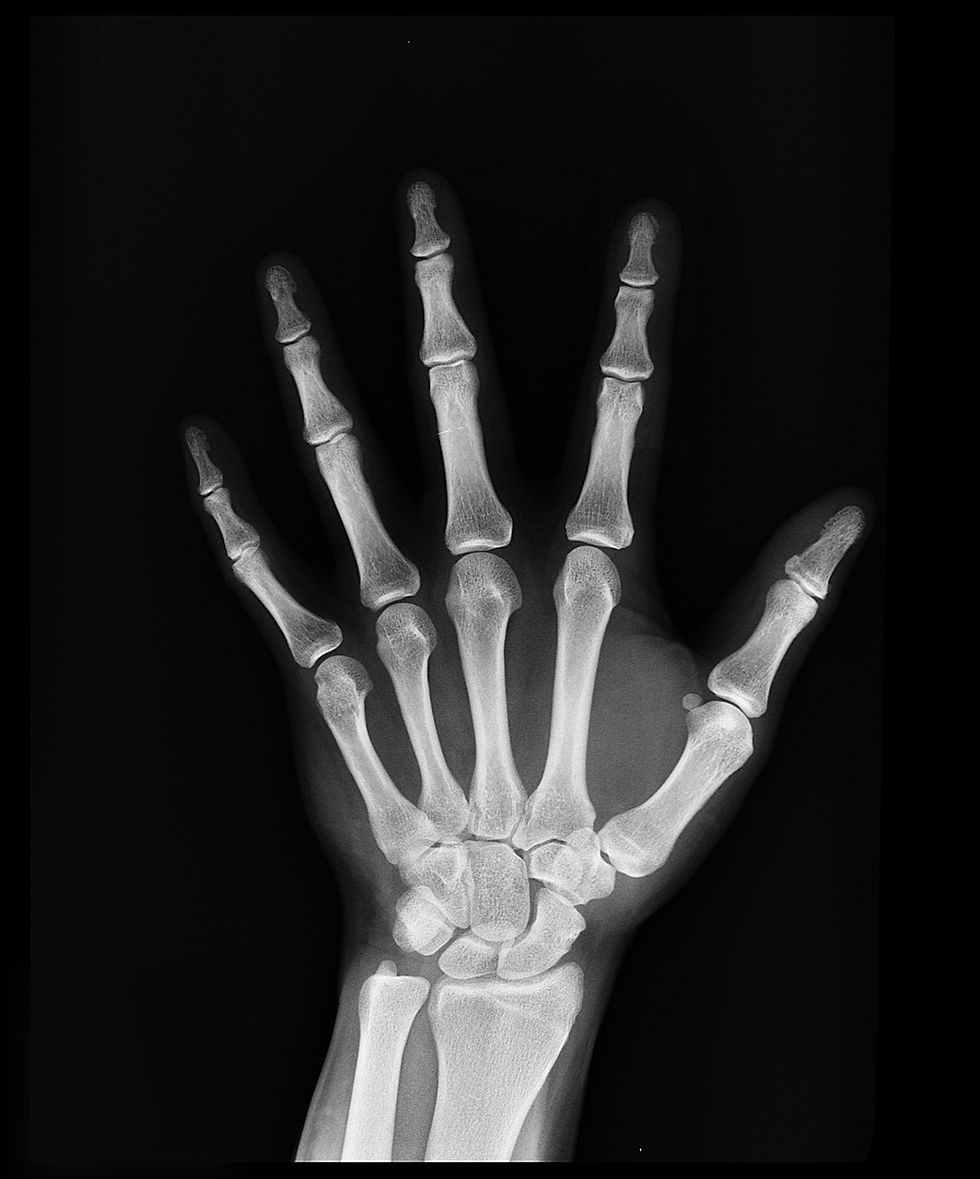

Carpal tunnel syndrome (CTS) is a common condition, affecting an estimated 4-10% of the population, with women being three times more likely than men to develop the condition (1,2). CTS occurs most commonly in people aged 40-60 years, but can affect anyone of any age

Several factors have been identified as potential risk factors for developing CTS, including repetitive use of the hand and wrist, pregnancy, obesity, arthritis, diabetes, and thyroid disease (3). Jobs that involve repetitive motions of the hand and wrist, such as typing, assembly line work, and using vibrating tools, also increase the risk of developing CTS.

While CTS is common, not everyone who experiences wrist or hand pain has CTS. It is important to consult with a healthcare provider for an accurate diagnosis and appropriate treatment plan.

Early diagnosis and treatment of CTS is important to prevent progression of the condition and reduce the risk of permanent nerve damage. Treatment options for CTS include non-surgical interventions such as splinting, physical therapy, and Chiropractic Care. Surgical options may be considered in more severe cases.